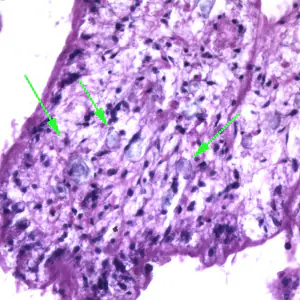

Migrating spargana cause various symptoms depending on the final location in the host. Spargana may locate anywhere, including subcutaneous tissue, breast, orbit, urinary tract, pleural cavity, lungs, abdominal viscera and the central nervous system. The migration in subcutaneous tissues is usually painless, but when spargana settle in the brain or spine a variety of neurological symptoms may occur, including weakness, headache, seizure, and abnormal skin sensations, such as numbness or tingling. If the inner ear is involved, the patient may experience vertigo or deafness. Occasionally, Sparganum proliferum can cause proliferative lesions in the infected tissue, with multiple plerocercoids present in a single site.

Proliferating spargana in groin tissue.